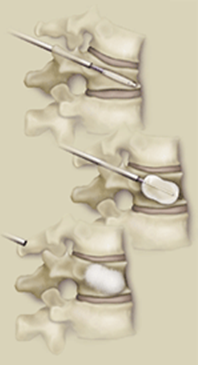

Kifoplasti Nedir?

İşlem vertebroplastiye benzemekle beraber, hedef omurganın içine önce balon yerleştirilmesi, bu balonun şişirilmesi, sonra söndürüldükten sonra oluşturulan boşluğa daha koyu kıvamlı tıbbi çimento verilmesi işlemidir.